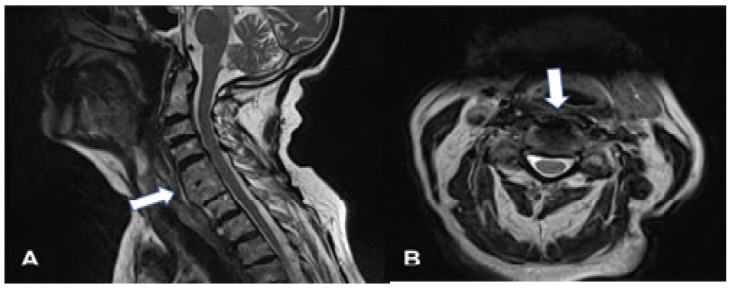

背景/目的:弥漫性特发性骨骼肥厚症(DISH)也被称为foretier - rotes - querol综合征。DISH的病因尚不清楚。DISH的特点是脊柱前纵韧带骨化。该疾病最常累及的区域是脊柱的胸椎区域。DISH在大多数情况下是无症状的。如果颈椎受累,最常见的症状是吞咽困难和呼吸困难。颈椎区的骨化最常发生在脊柱的下节段。病例报告:作者报告了一位92岁的女性病毒症患者(身体质量指数(BMI)为17;在过去的6个月里她的体重减少了13%)。患者行前骨赘C2-T1切除术。结果:在一年的随访中,患者体重增加(BMI-20),并恢复了固体食物的摄入能力。据我们所知,这是接受DISH手术治疗的年龄最大的患者。结论:老年患者如出现吞咽困难或呼吸困难,应进行颈椎检查。如果诊断为DISH是安全的,则应考虑有效的手术治疗。

Background/Objectives: Diffuse idiopathic skeleton hyperostosis (DISH) is also known as Forestier-Rotes-Querol syndrome. The etiology of DISH is unknown. DISH is characterized by ossification of the anterior longitudinal ligaments of the spine. The area most frequently involved in the disease is the thoracic region of the spine. DISH in most cases is asymptomatic. If the cervical spine is involved, the most common symptoms are dysphagia and dyspnea. The ossifications in the cervical region of the spine are localized most frequently in its lower segments. Case presentation: The authors present the case of a 92-year-old cachectic female patient (body mass index (BMI) of 17; lost 13% of her body weight within the last 6 months). The patient underwent resection of the anterior osteophytes C2-T1. Results: At one-year follow up, the patient had gained weight (BMI-20) and regained her ability to consume solid products. To our knowledge, this is the oldest patient treated surgically for DISH. Conclusions: If dysphagia or dyspnea appears among elderly patients, cervical spine inspection should be conducted. If DISH is diagnosed safe, effective surgical treatment should be considered.